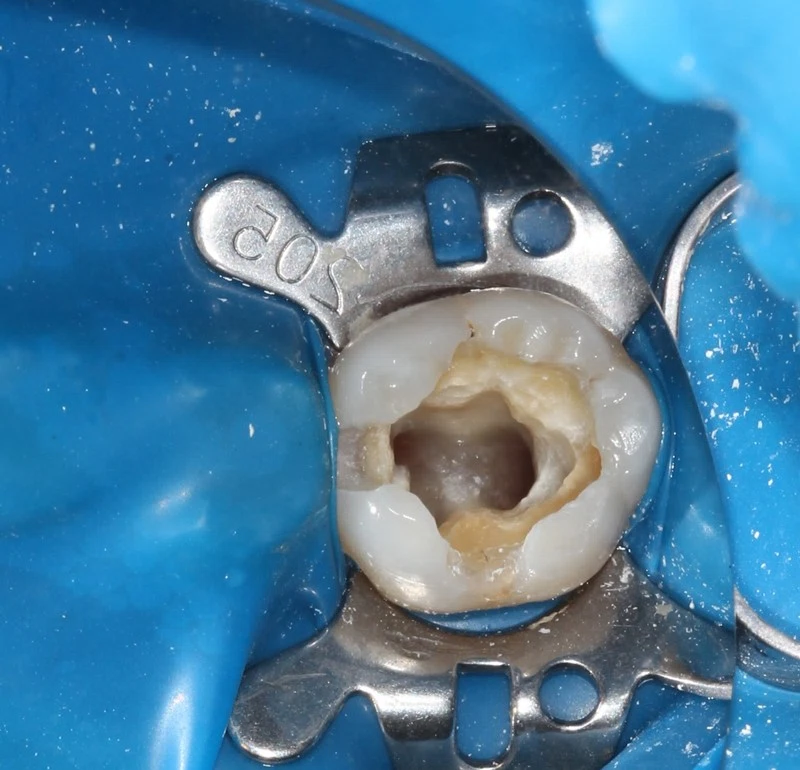

患者因劇烈牙痛就診。經檢查,確認為嚴重蛀牙已經穿透牙釉質與牙本質,感染深達牙髓腔神經,引發不可逆恢復的牙髓炎。

- 治療步驟: 必須立即進行根管治療(俗稱抽神經),清除發炎或和壞死的牙髓組織,徹底清創並緊密封填根管系統,以保留這顆珍貴的自然牙。

- 無菌保障: 我們在治療過程中全程使用橡皮布障隔離患齒和口腔環境的細菌,創造無菌的治療環境,大幅提高治療的成功率和預後。

治療前 / 治療後對比